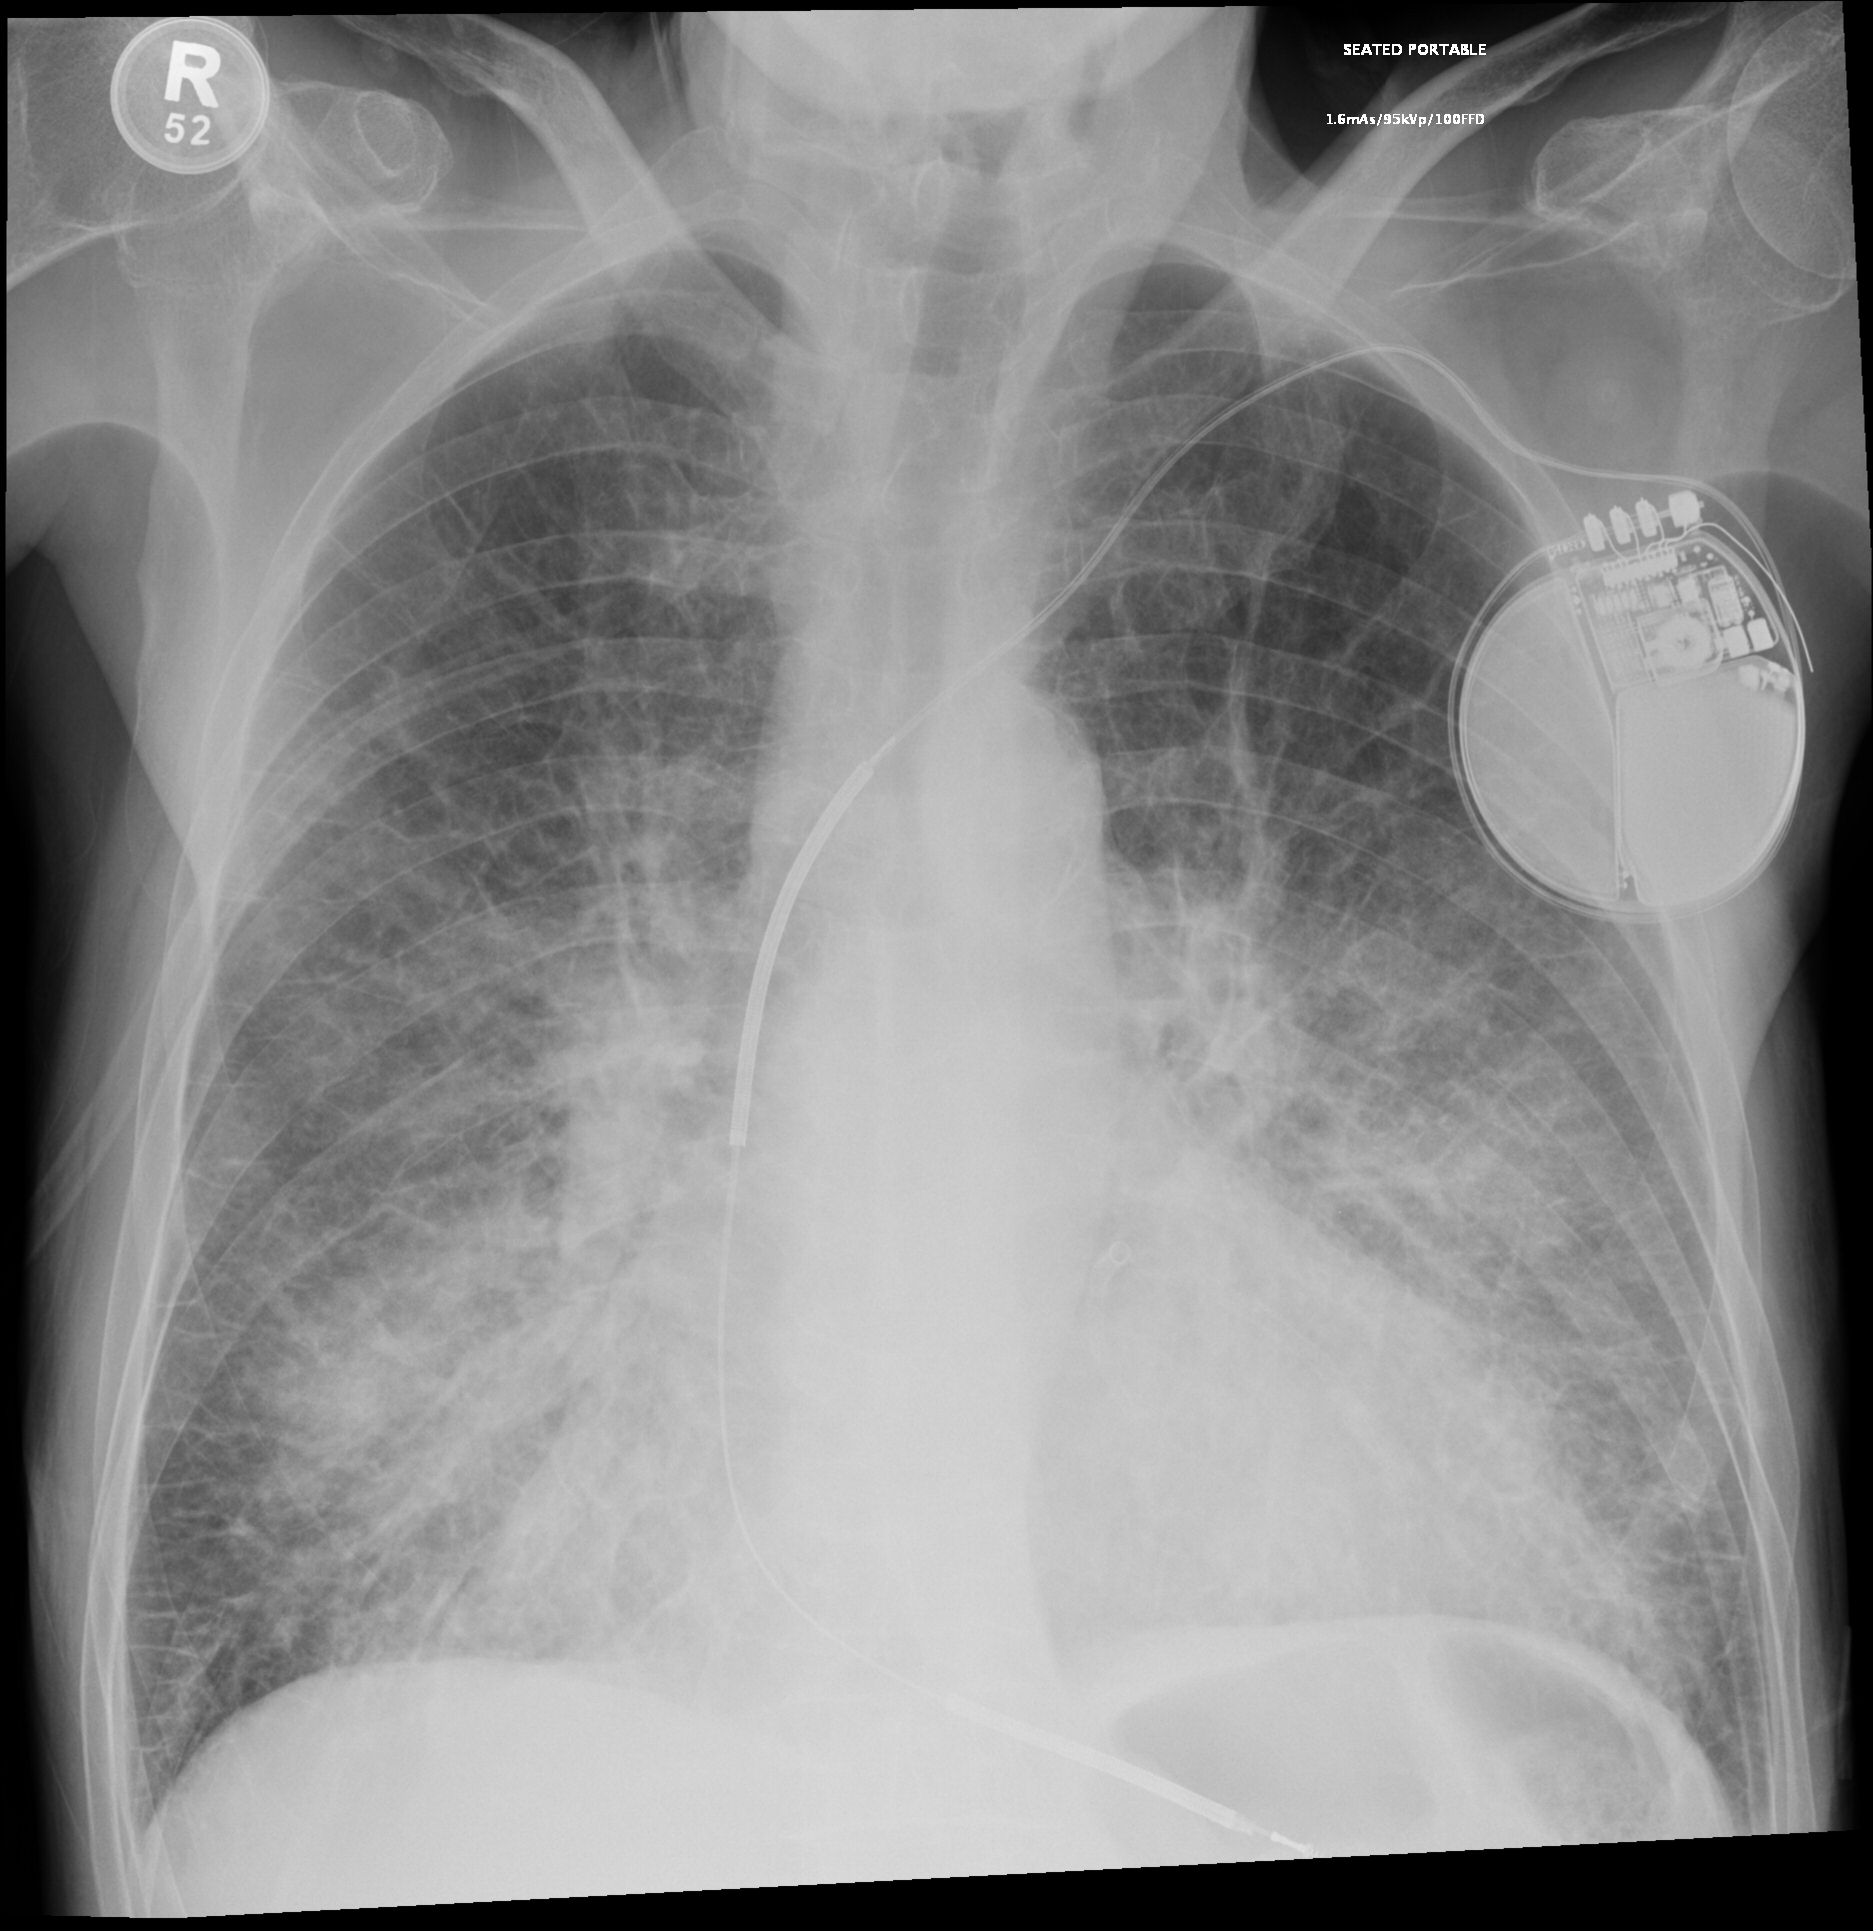

Ein Patient mit Dyspnoe stellt sich in der ZNA vor. Es wird ein Röntgen-Thorax (p.a.-Projektion im Stehen) angefertigt. Was erkennen sie darauf?